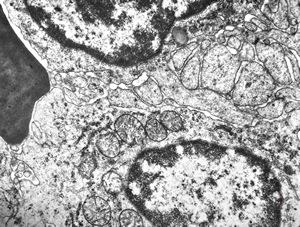

F,68y. | spleen - undefined myelinoid inclusions - clin. susp. leukemia

F,68y. | spleen - myelinoid inclusions - clin. susp. leukemia